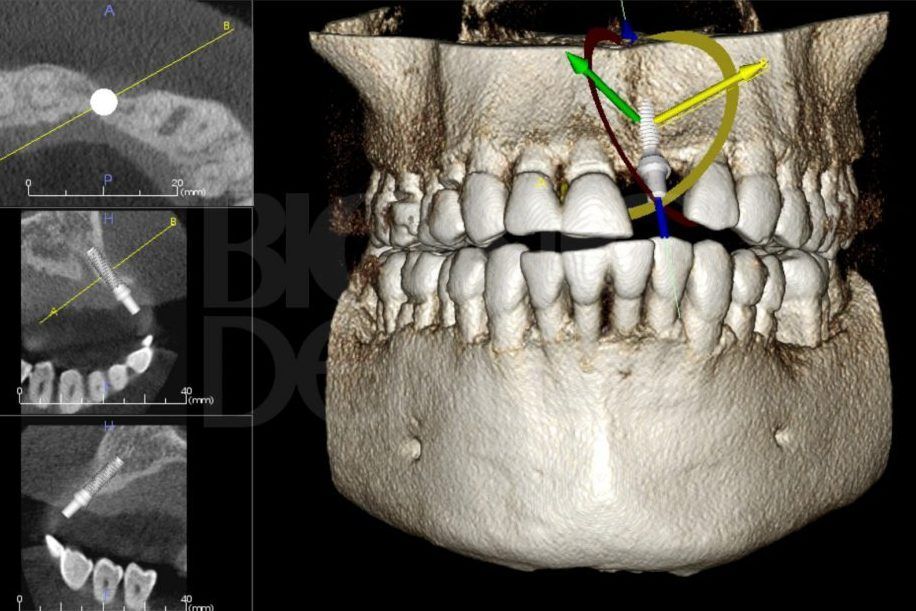

Рентгенологический снимок всей зубочелюстной системы.

Первичная консультация – это то, с чего начинается каждое лечение. Ее предлагают пройти всем пациентам, которые впервые обращаются в клинику. Она очень важна, особенно если планируется большая и сложная работа: имплантация, протезирование и т.д.

На первичной консультации во время беседы мы выясняем проблемы, запросы и пожелания пациента. В обязательном порядке после осмотра проводим диагностику, чтобы получить всю необходимую информацию о состоянии зубов. Мы составляем фотопротокол. Фотографии позволяют детально изучить проблемные зоны, а пациенту – наглядно увидеть проблемы. В дальнейшем можно легко оценить результаты до и после.